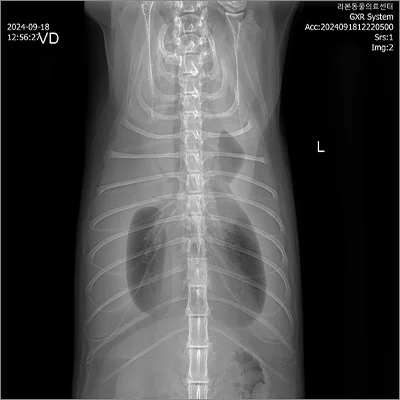

PDA 전

PDA 후